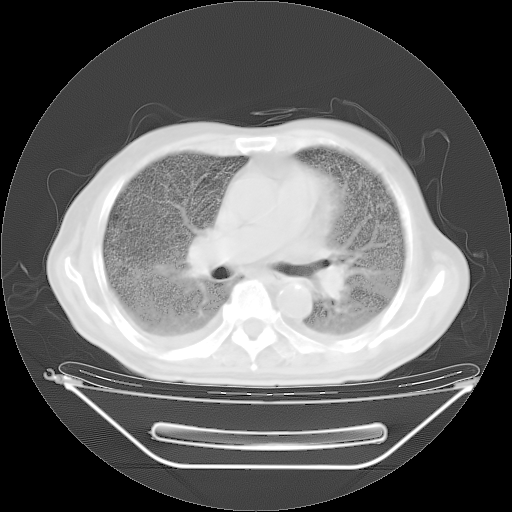

今天复查肺部CT,发现双肺广泛磨玻璃样改变。所以我把3月19日和5月9日相隔50天的肺部CT上传。请大家会诊。

2009年3月19日肺部CT片。

5月9日肺部CT(在4月27日齐鲁医院肺部CT描述部分肺组织磨玻璃样改变,12天后肺组织广泛磨玻璃样改变)